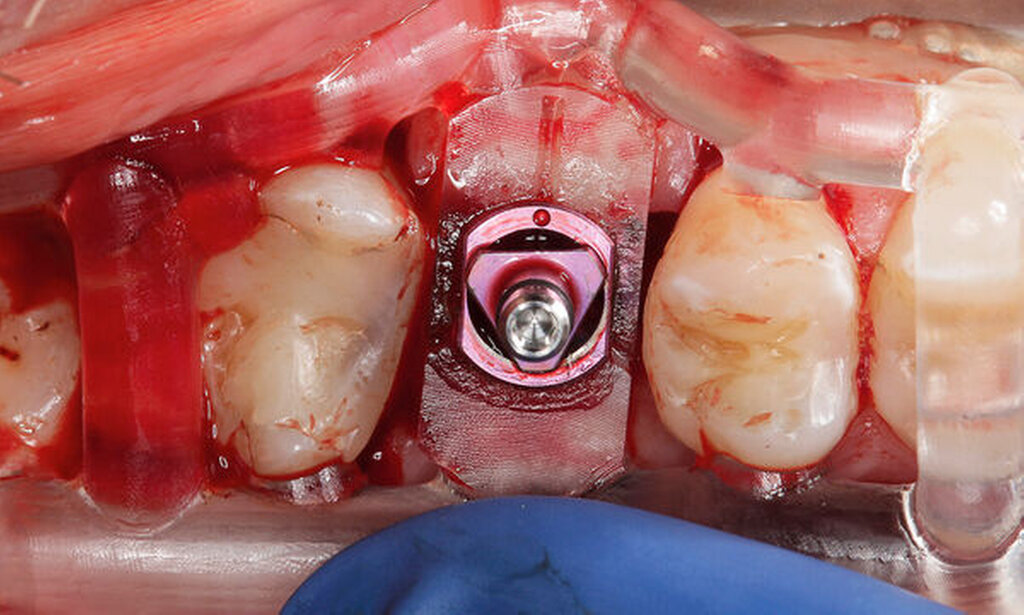

Im vorliegenden Patientenfall wurde die Implantation statisch navigiert mithilfe einer Bohrschablone und einer voll geführten Insertion durchgeführt (Abbildung 3). Dafür wurde der STL-Datensatz der Bohrschablone nach der Konstruktion in der IPS durch einen spezialisierten Mitarbeiter des Servicepartners DEDICAM (CAMLOG Vertriebs GmbH, Wimsheim) für die Bohrschablone zur Verfügung gestellt. Die Herstellung der Schablone erfolgte mithilfe eines 3-D-Druckers (Form 3, Formlabs GmbH, Berlin) im zahntechnischen Labor der Charité – Universitätsmedizin Berlin. Alternativ hierzu kann die Schablone auch vollständig fertig gestellt beim entsprechenden Anbieter bestellt werden.

Die genaue Gestaltung der Bohrschablone ist abhängig vom Bohrprotokoll und der Führungsmethode des jeweiligen Implantatherstellers. Beim vorliegenden Patientenfall und Implantatsystem fanden die Aufbereitung des Implantatbetts und die Implantatinsertion durch eine in die Schablone eingeklebte Metallhülse statt (Abbildungen 4 und 5). Sowohl die Bohrer als auch die Einbringpfosten erreichen dabei einen definierten Tiefenstopp (Abbildung 4).